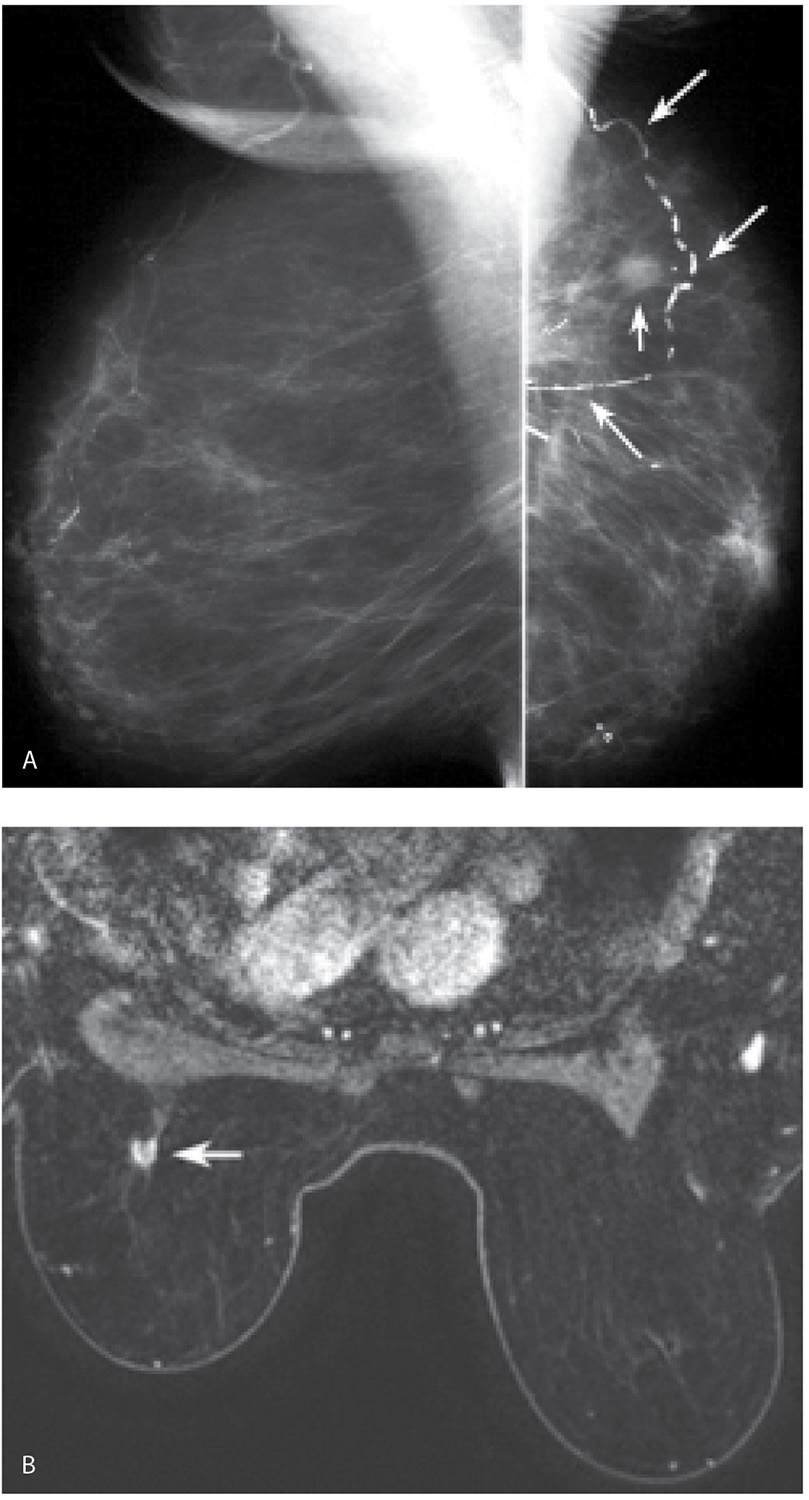

US (A) Spiculated breast mass with strong Posterior Acoustic Shadowing

Malignant spiculated breast masses Dynamic contrast enhanced MR (DCE Spiculated Margins Breast Mass It has been our experience that many cancers that appear ill. Spiculated margins are frequently a feature of malignant breast lesions and radial scars. Benign and malignant characteristics of breast lesions at ultrasound allow the classification as either malignant,. If a mass has spiculated margins, it has an 80% chance of being malignant. A spiculated mass is a centrally dense. Spiculated Margins Breast Mass.

Malignant spiculated breast masses Dynamic contrast enhanced MR (DCE Spiculated Margins Breast Mass A spiculated mass is a centrally dense lesion seen on mammography with sharp lines radiating from its margin. It has been our experience that many cancers that appear ill. Benign and malignant characteristics of breast lesions at ultrasound allow the classification as either malignant,. Spiculated margins are frequently a feature of malignant breast lesions and radial scars. If a mass. Spiculated Margins Breast Mass.